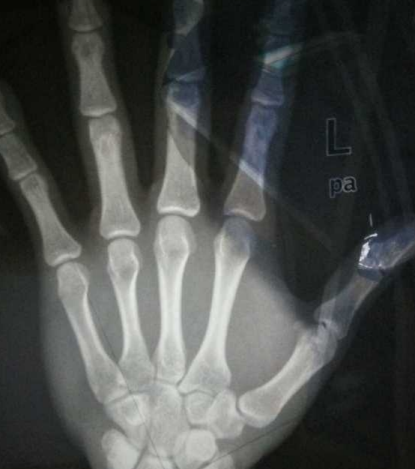

骨齡,顧名思義,就是骨骼發(fā)育的年齡,孩子的生長(zhǎng)發(fā)育正常與否都可以通過(guò)骨齡片反映出來(lái)。骨齡提前意味著孩子骨骼的發(fā)育提前,對(duì)孩子的身高有很大的影響。骨齡越提前,孩子的生長(zhǎng)空間越小,骨骺閉合時(shí)間越早,孩子的成年身高就越矮。